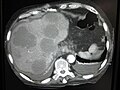

Tests include a blood test to look for raise liver enzymes.[1] Ultrasound, CT scan, MRI scan and PET scan are used to investigate the origin of the cancer and to define the extent of disease.[1][4] Taking a sample of liver tissue, guided by medical imaging, may confirm the diagnosis.[2] Treatment generally involves treating the original cancer and cutting out parts of affected liver.[1][4] Other therapies include chemotherapy, radiofrequency ablation, thermal therapy and cryotherapy.[1] Medicines such as bevacizumab and cetuximab and immunotherapeutic agents, may be other options.[4] The choice of treatment and the outcome may be guided by genetic tests.[4]

Tests include a blood test to look for raise liver enzymes.[1] Ultrasound, CT scan, MRI scan and PET scan are used to investigate the origin of the cancer and to define the extent of disease.[1][4] Taking a sample of liver tissue, guided by medical imaging, may confirm the diagnosis.[2]